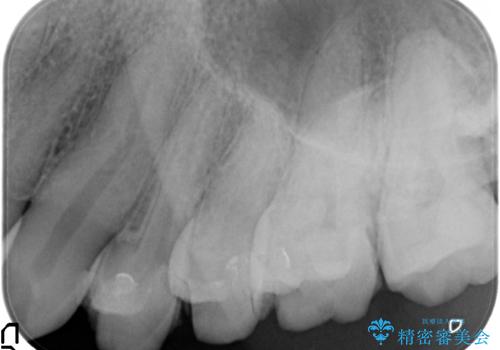

- 他院で治療途中で放置したところを治療したいとご来院されました。

仮づめはフロスもできないため、不潔になりやすく長期的には虫歯になりやすいです。

仮づめの状態でしたが、そこまで中は虫歯になっておらず、神経の治療も不要でした。